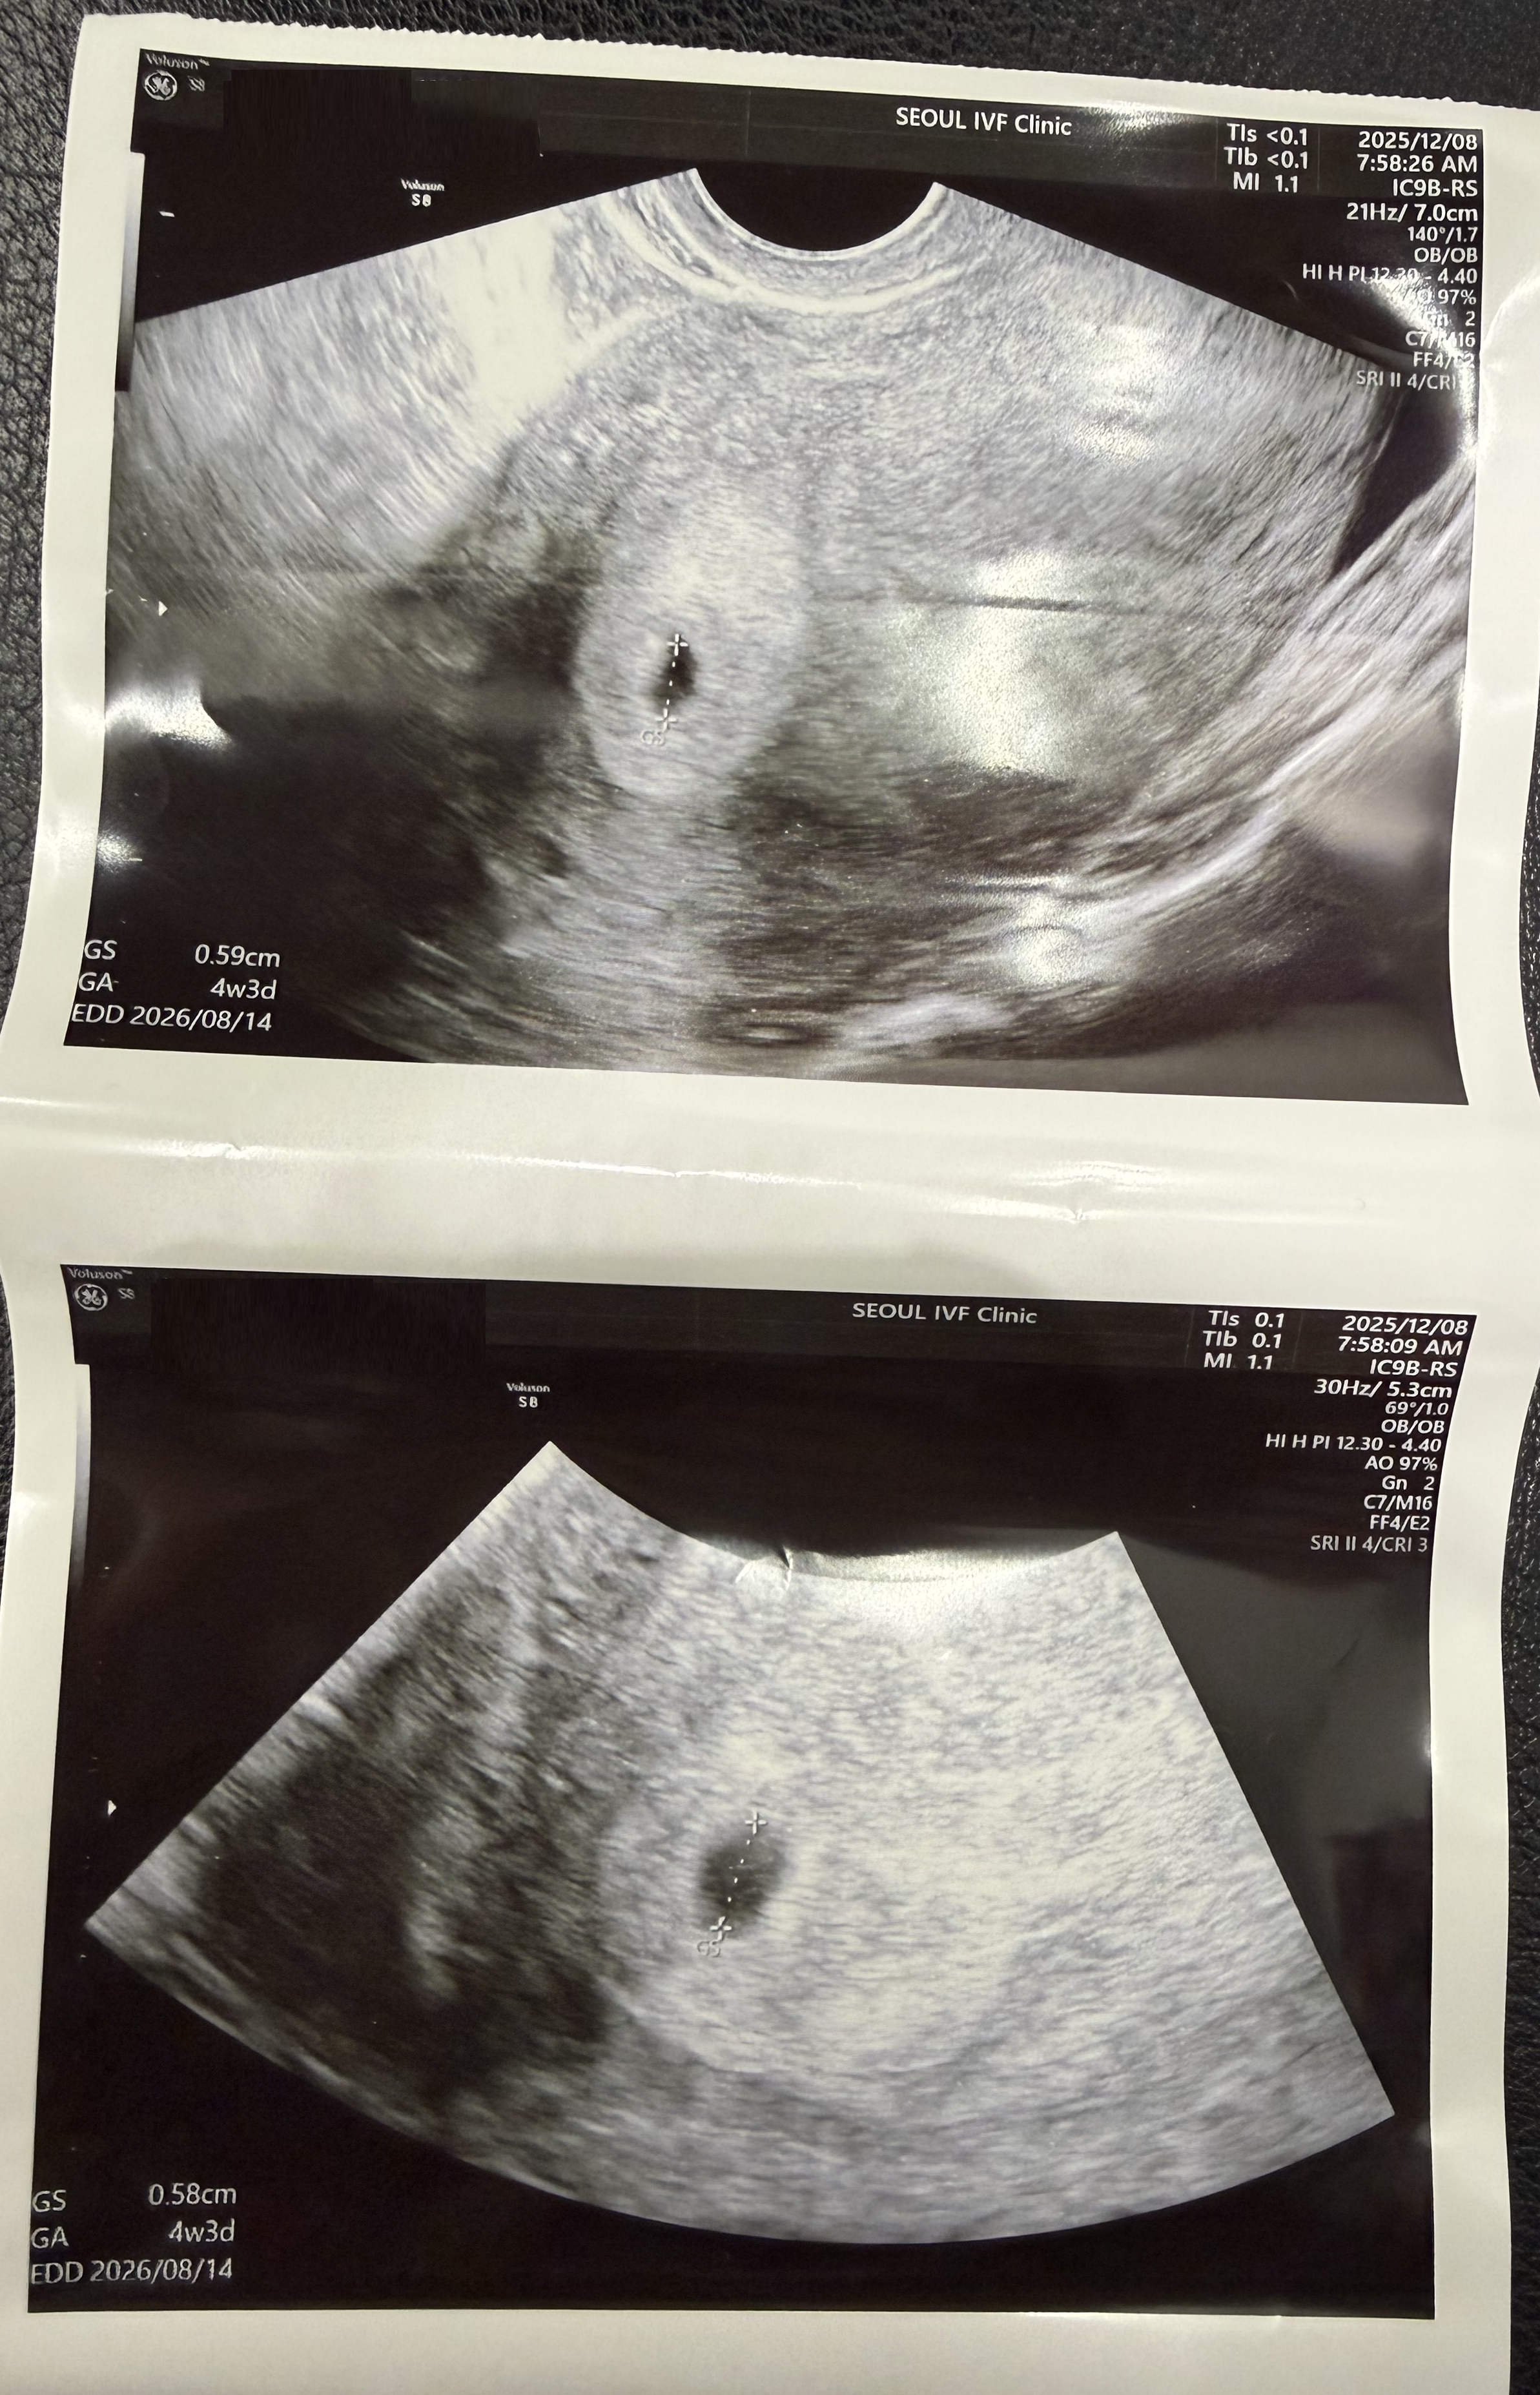

| 가슴 떨리는 임신 이야기를 공유해 주세요. | 결혼 후 피임을 하지 않으면 자연스럽게 임신이 될 거라 생각했지만 그렇지 않아 서울아이비에프여성의원을 찾게 되었습니다. 인공수정 1차 실패 후 시험관 시술을 선택했고, 시험관 1차에 임신에 성공할 수 있었습니다. |

| 치료 도중 느꼈던 가장 기뻤던 순간과 절망적인 것들은 무엇인가요? 잊지 못할 경험이 있나요? | 가장 기뻤던 순간은 임신 테스트기에서 두 줄을 확인했던 날입니다. 다음 날이 시험관 피검사 날이었는데, 실제 임신 수치를 확인했을 때의 기쁨은 아직도 잊히지 않습니다. 아기의 심장소리를 처음 들었을 때 역시 평생 기억에 남을 순간이었습니다. 반면 인공수정 1차가 실패했을 때와, 수많은 시험관 주사 과정, 임신 후에도 프롤루텍스 주사를 계속 맞아야 했던 시간은 가장 힘들었던 기억으로 남아 있습니다. 나팔관조영술과 자궁이 휘어 있는 상태로 인해 인공수정과 배아이식이 쉽지 않았던 점도 큰 부담이었습니다. |